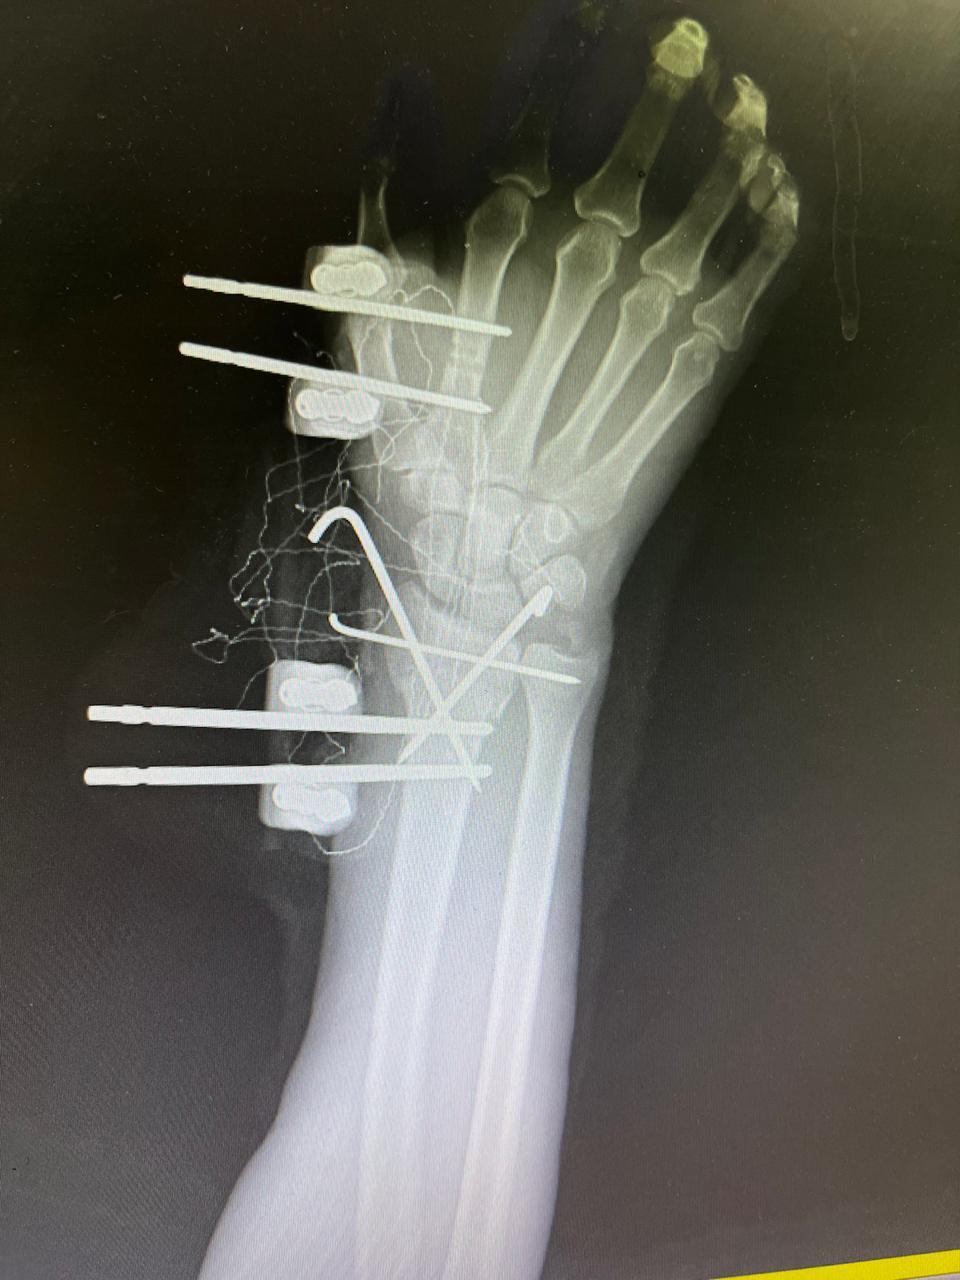

- إجراء عمليات جراحية معقدة و دقيقة في مجال العظام و المفاصل و الكسور و الإصابات ، رغم الضغط الكبير على المستشفى و أعداد المراجعين الكبيرة.

- تطبيق تقنيات جراحية حديثة و متقدمة، و ذلك في ظل التحديات التي يواجهها الفريق بسبب أعداد المرضى و المراجعين الكبيرة.

- تقديم خدمات جراحية عالية الجودة و آمنة للمرضى، رغم الضغط الهائل على المستشفى في العيادة و القسم و الطوارئ .